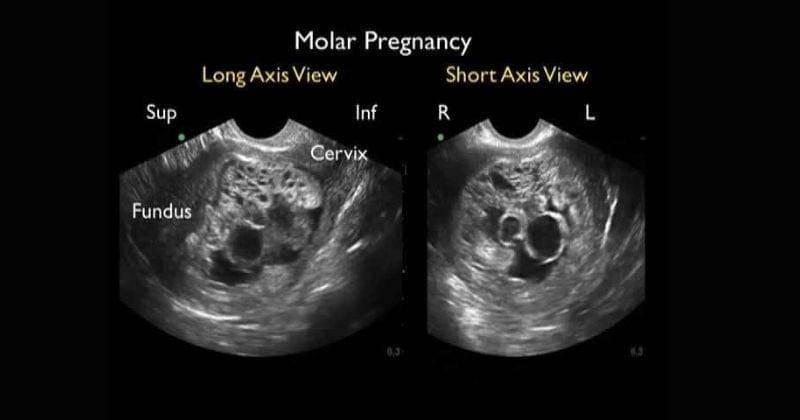

4. Kehamilan molar

Kehamilan molar atau biasa disebut hamil anggur adalah kondisi yang sangat langka dialami oleh ibu hamil.

Kehamilan molar adalah kondisi di mana sel telur yang dibuahi gagal tumbuh menjadi janin. Dalam kasus khusus, jaringan ini bisa berkembang sebagai kanker dan menyebar ke bagian tubuh yang lain.

Adapun gejala dari kehamilan molar adalah mual dan muntah hingga yang terparah adalah pembesaran rahim yang cepat. Segera waspada untuk kondisi ini.